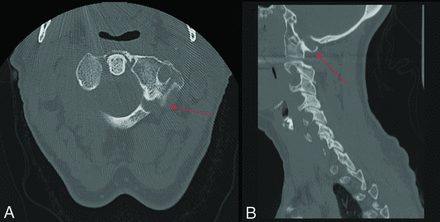

Fracture-negative, radiologist true negative, CNN false positive case example. Axial (A) and sagittal (B) cervical spine CT images demonstrate congenital thinning and incomplete fusion of the left C1 lamina. Red arrows demarcate congenital thinning and incomplete fusion. This case example illustrates a limitation of the AI algorithm to mistake common congenital anomalies for fractures if the image contains linear bony lucency extending into the cortex.

Fracture-negative, radiologist true-negative, CNN false-positive case example. Axial cervical spine CT image demonstrates a postsurgical defect involving the right lamina secondary to laminoplasty. Red arrow demarcates postsurgical defect. This case example illustrates a drawback of the algorithm to fail to differentiate postsurgical changes from fractures.